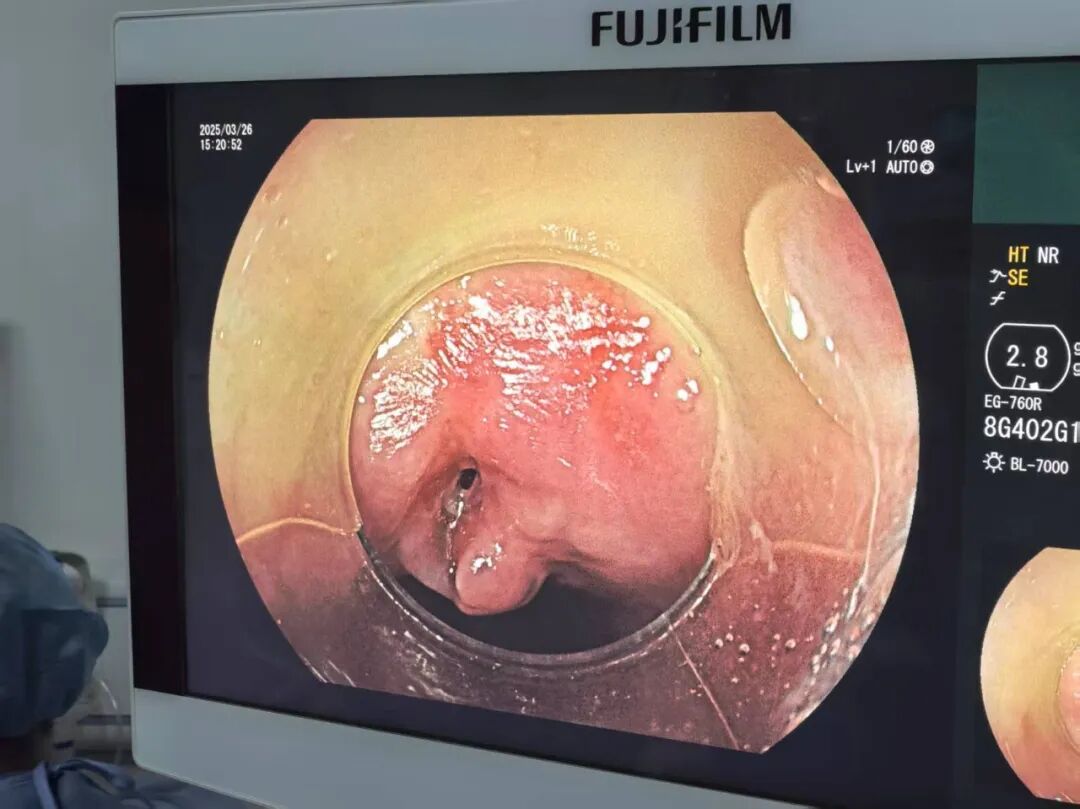

患者王某,入院前半月因吃鸡骨头时不慎卡住,此后便出现吞咽困难及疼痛症状且逐渐加重,伴咯血及呼吸困难,咽喉部疼痛不适,遂来区人民医院胸外科就诊,行胸部CT发现鸡骨尖锐端已穿透食管壁,导致食道穿孔,若不及时处理,可能引发脓胸、大出血甚至感染性休克。

3月26日,手术在消化内科、麻醉科、呼吸与危重症医学科协作下顺利完成,术中探查发现鸡骨尖端嵌入食管中段,周围黏膜严重水肿,穿孔处可见脓性分泌物,通过密切合作,顺利取出长约3cm的尖锐骨片。